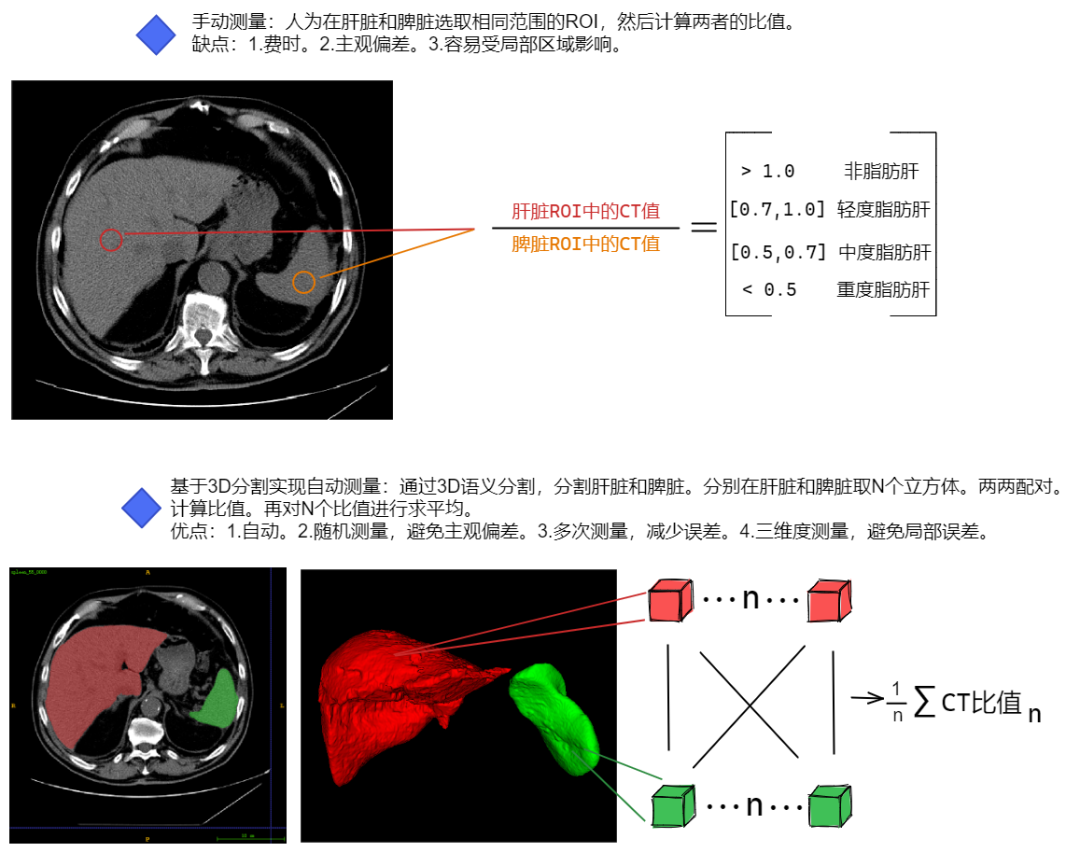

现在人们的日常生活方式和饮食结构发生了巨大的变化,大概就是吃好了,动少了。体内的过量的甘油三酯无法代谢,最终聚集在肝细胞内,导致人体中正常肝脏逐步变成脂肪肝。长期患有脂肪肝可能会导致肝硬化,并最终增加患慢性肝病的风险。医学影像学领域可以通过CT或者B超技术来判断患者是否患有脂肪肝,其中CT的脂肪肝检出比例高于B超,其用于诊断脂肪肝时准确率更高、特异性更强。在CT检查中,主要是通过计算肝脏与脾脏的CT值的比值来确定患者是否患有脂肪肝以及严重程度。根据中华医学会肝病学分会制定的标准,肝、脾CT比值大于1为正常肝脏,CT比值在[0.7,1.0]之间为轻度脂肪肝,[0.5,0.7]之间为中度脂肪肝,小于0.5为重度脂肪肝。

在日常工作中,放射医师需要手工选择肝脏和脾脏的最大层面,在一定范围内进行 ROI 的选取,之后计算 ROI 范围内肝脏和脾脏的CT总值以及计算两者 ROI 范围内CT总值的比值,从而确定患者是否患有脂肪肝。这个过程需要投入较多的工作量。

目前,深度学习技术中的语义分割正被广泛应用于医学领域。该技术可以通过训练模型来预测出影像中的不同组织类型的精确边界、位置和区域,在腹部CT上自动获得肝脏和脾脏的分割结果,对肝脏和脾脏多次随机取出一定体积的立方体来计算CT总值的比值,从而评估被检测者是否有脂肪肝以及脂肪肝的严重程度。这种方式减轻医生的工作强度,也避免人为的主观性带来的偏差。

如下图展示人工测量和基于语义分割自动测量之间的优劣。

医学临床上进行诊断时会人为选择CT平扫肝、脾显示最大层面,各选取边长为1.0cm以上的正方形 ROI 对肝、脾取CT值。本项目为了降低随机选取 ROI 时可能纳入肝内血管和伪影部分,影响计算肝脾比值结果的真实性,提出如下解决方法:1.增加随机取出立方体 ROI 的个数;2.两两配对,增加肝脾比值的样本。